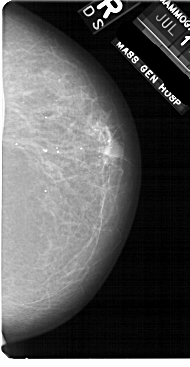

A_1868_1.LEFT_MLO

LEFT_MLO LINES 5491 PIXELS_PER_LINE 3016 BITS_PER_PIXEL 12 RESOLUTION 43.5 OVERLAY